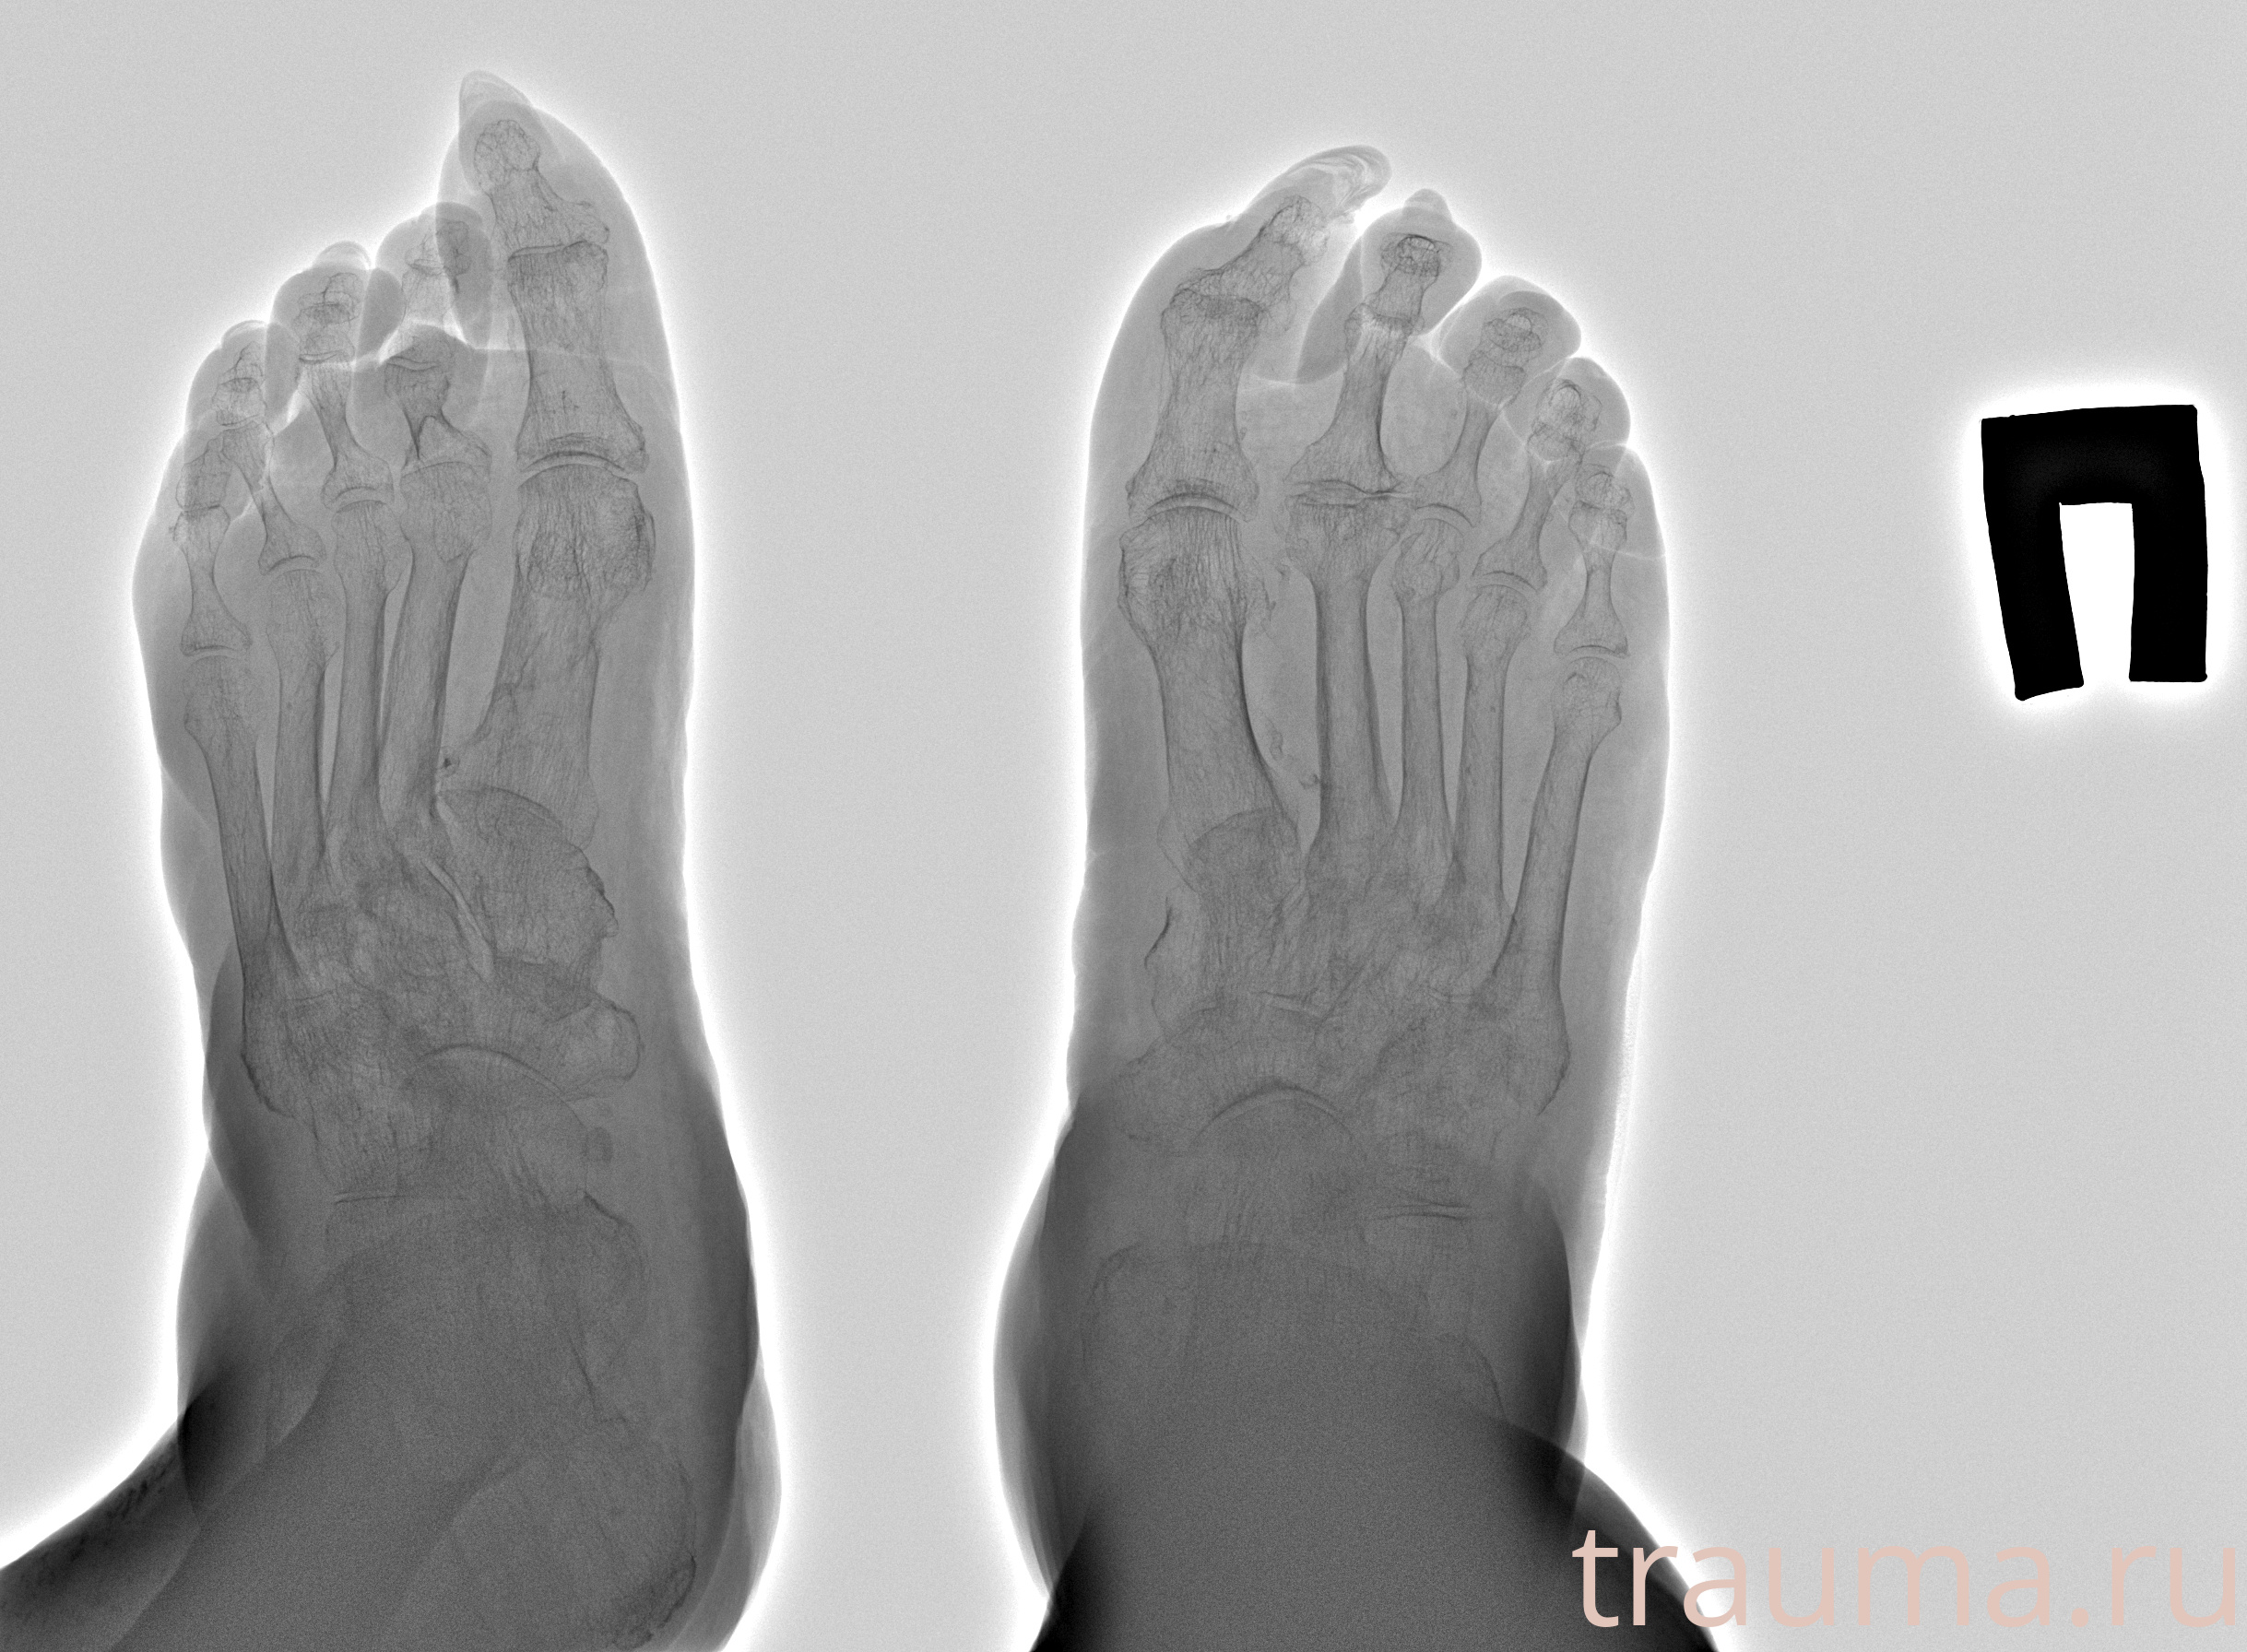

Рентгенограммы

Рентген на дому: по вашему адресу приезжает врач-рентгенолог, травматолог-ортопед с мобильным рентгеновским аппаратом, проводит диагностику травмы или заболевания, делает необходимые рентгенограммы, дает рекомендации по дальнейшему лечению. Получить качественные снимки в домашних условиях возможно благодаря уникальной методике, разработанной МосРентген Центром для института  Склифосовского